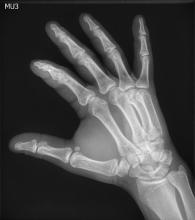

The remaining users of film and computed radiography (CR) may get some carrot, if they transition to digital radiography (DR). It may come in the form of improved productivity, reduced X-ray dose to patients and better image quality. But the legislation that may spur the transition is all stick.